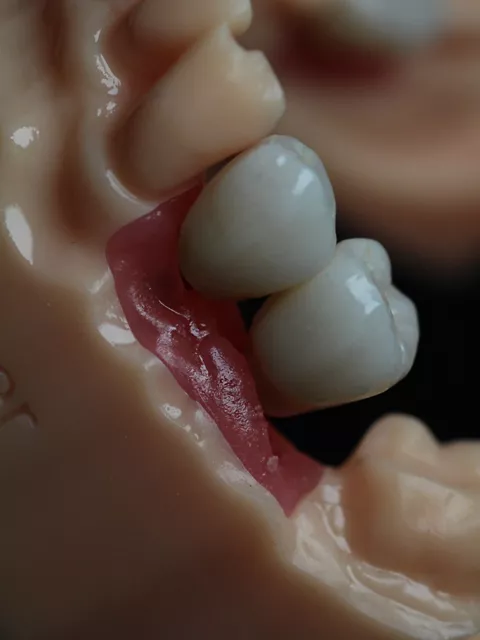

In contrast, the adjacent LL4 site presented more favorable bone conditions and achieved high primary stability at placement, enabling immediate placement of a HealFit® anatomical healing abutment to establish transmucosal shaping from surgery. After 3 months, osseointegration was satisfactory at both sites, though soft‑tissue maturation was notably superior at LL4, consistent with early guided soft‑tissue contouring.

Similarly, at LL6 the implant exhibited insufficient primary stability (< 20 N·cm) and was placed subcrestally with a cover screw for submerged healing, while the mesial implant at LL5 (when stability was adequate > 45 N·cm) received a HealFit® abutment to support soft‑tissue maturation during healing (7.).

7. Distal implant placed with a cover screw, and mesial implant restored with a HealFit® SH anatomical healing abutment.

7

In contrast, the mesial implant had achieved adequate primary stability at surgery, allowing the use of a HealFit® SH anatomical healing abutment from the time of placement. This resulted in progressive transmucosal shaping without the need for additional surgical intervention. At re‑evaluation (8.), peri‑implant soft‑tissue maturation was already complete at this site, illustrating the clinical advantages of immediate transmucosal conditioning, including reduced need for second‑stage surgery, minimised soft‑tissue trauma, improved emergence profile development, and a more streamlined prosthetic workflow.

Soft‑tissue healing differed notably between the two sites. The mesial implant restored with a HealFit® SH abutment showed thicker, well‑adapted peri‑implant mucosa with minimal erythema inflammation and a stable, guided emergence profile, reducing the need for secondary tissue conditioning. In contrast, the distal implant with a traditional healing abutment demonstrated localized redness, a compressed circular healing pattern, and no guidance of soft‑tissue contour, features commonly associated with conventional implant exposure techniques, which can produce increased soft‑tissue reactivity and later need for tissue shaping.

12a. 12b. 12c. 12d. 12e. Soft‑tissue healing comparison: HealFit® SH shows anatomic, well‑shaped mucosa, while the conventional healing screw displays a flat, compressed circular pattern.